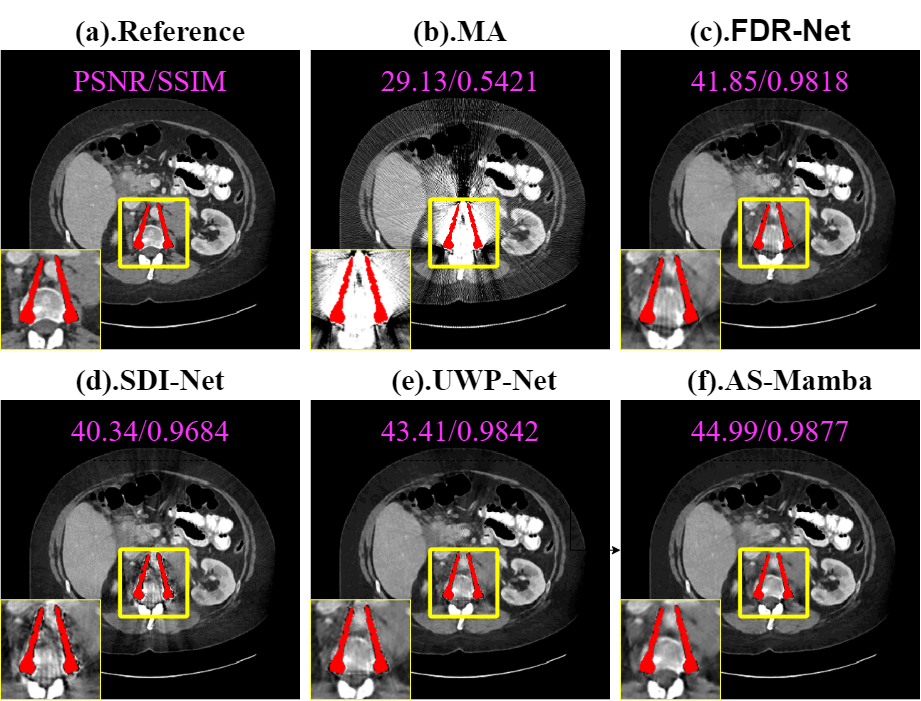

Frequency-Decoupled Reconstruction Network (FDR-Net): This model performs the wavelet decomposition and dual-branch processing but omits the subsequent iterative refinement. The output from the initial reconstruction is the final result.

Spatial-Domain Iterative Network (SDI-Net): This model removes the entire wavelet-domain processing pipeline. It directly processes the concatenated input with a U-Net, followed by the iterative refinement stages.

Unified Wavelet Processing Network (UWP-Net): This model performs the wavelet transform but does not decouple the coefficients into low and high frequencies. Unified network processes the wavelet coefficients together before the inverse transform.

| FDR-Net | 40.53 / 0.9754 | 42.84 / 0.9825 | 44.13 / 0.9864 | 42.50 / 0.9814 |

| SDI-Net | 38.54 / 0.9513 | 40.65 / 0.9634 | 42.14 / 0.9712 | 40.44 / 0.9620 |

| UWP-Net | 41.83 / 0.9792 | 43.94 / 0.9863 | 45.23 / 0.9894 | 43.67 / 0.9850 |

| AS-Mamba | 43.24 / 0.9814 | 45.12 / 0.9873 | 46.64 / 0.9912 | 44.97 / 0.9866 |

Quantitative results in Table 3 show that AS-Mamba consistently outperforms all variants. Specifically, SDI-Net exhibits the lowest metrics, confirming that pure spatial methods struggle to separate spatially intertwined artifacts and tissues. The superiority over UWP-Net validates the necessity of frequency decoupling, as uniform processing fails to effectively target high-frequency streaks. Furthermore, FDR-Net falls short of the full model, indicating that image-domain iterative refinement is essential for enforcing global consistency. Visual comparisons in Fig. 10 confirm these findings, where AS-Mamba achieves the sharpest restoration compared to the blurred or artifact-prone baselines.